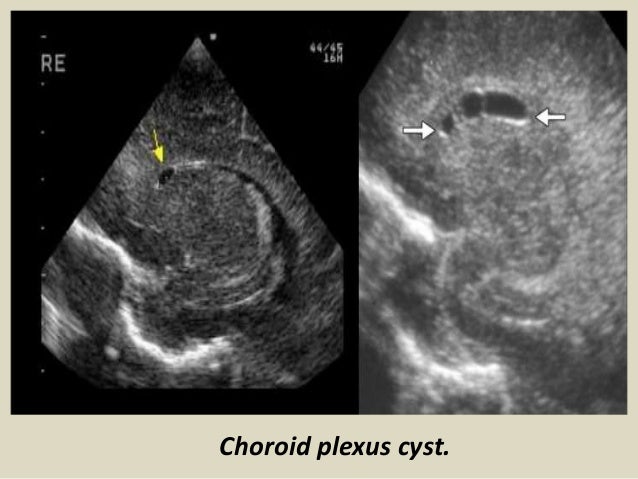

32. 32. Choroid plexus cysts. Common, 3% prevalence. Glomus. < 1cm, unilateral = insignificant. > 1cm, bilateral = increase associated with chromosomal abnormalities.

36. 36. Choroid plexus cyst.